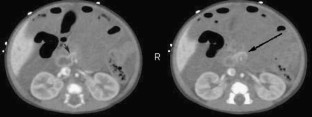

Enhanced CT perfusion cut-off sign in midgut volvulus

We present a case of malrotation with midgut volvulus in an infant in which we discovered a unique CT sign called the perfusion cut-off sign. We hope this case will help establish this crucial diagnosis in other cases.

Fig. 2